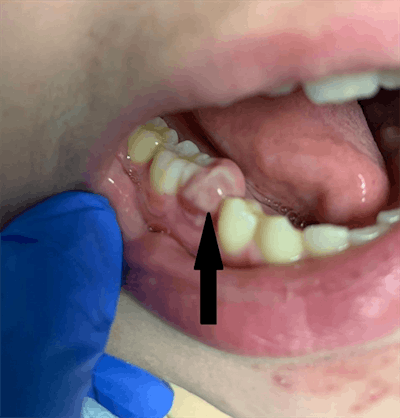

The lower right first premolar was confirmed missing during examination of the oral cavity. However, there was a 1 x 1-cm tender indurated bonelike buccal vestibular swelling on the lower right jaw adjacent to the missing tooth site. Also, a 5 x 5-mm nonfluctuant pink gum overgrowth lesion was seen at the lower right first premolar site, according to the authors.